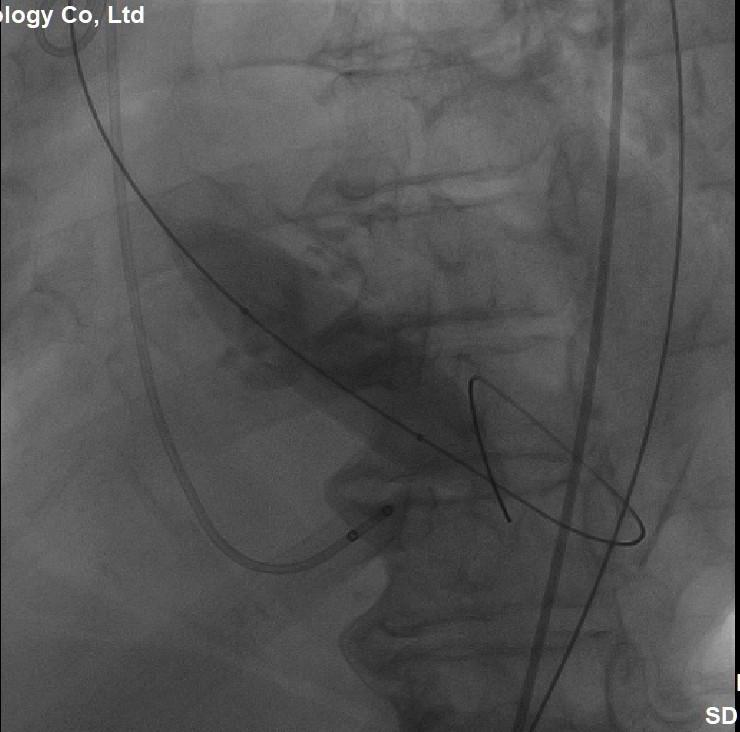

(图4,选用22mm的球囊,扩张狭窄的主动脉瓣)

经过充分细致地准备,多学科积极协作,在张希全主任指导下,心血管外科谷兴华主任医师、急诊心内科李传保主任医师、心血管外科孙厚荣副主任医师及团队成员在绿帽社复合手术室实施手术。根据患者的病情特点,术中做好各种应急预案,备好体外循环,维持血流动力学平稳。根据术前CT分析和术中主动脉根部造影情况(图1、图2、图3),选择最佳投照体位。先选用22mm球囊,临时起搏180次/分,扩张重度狭窄的主动脉瓣(图4)。再选用24mm的介入主动脉瓣膜,造影、定位、临时起搏、顺序释放介入瓣膜,造影及心脏超声检查示:人工瓣膜位置形态满意,瓣膜启闭功能正常,主动脉瓣无瓣周分流,跨瓣压差降至8mmHg(图5、图6)。术后1小时,麻醉清醒,术后8小时顺利脱机拔管,术后第2天转入普通病房,病情稳定,治愈出院。